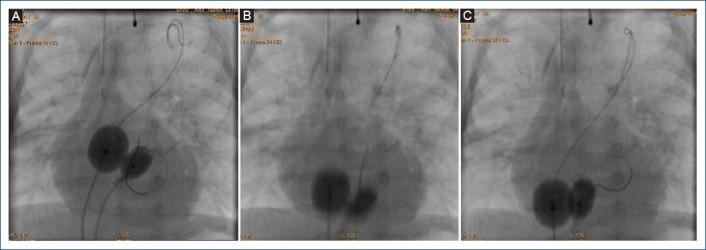

双“动态”球囊房间隔造口术。针对房间隔增厚病例对拉什金德医生技术的新改良。

Double "dynamic" balloon atrial septostomy. New modification of Dr. Rashkind's technique for cases with thickened interatrial septum.

Balloon atrial septostomy (BAS) is a palliative procedure mainly for newborns with transposition of the great arteries, currently, this procedure has a class IA recommendation. However, in some cases, this procedure does not achieve an adequate interatrial defect, due mainly to a thickened interatrial septum, this situation led to the development of various techniques to tackle this problem. Therefore, we made a modification to the original technique using two balloons simultaneously instead of one. The objective of this study is to analyze the results of this new modification to the traditional technique (with one balloon) as an alternative for cases with thickened interatrial septum.

Six patients were identified (median age 35 days, median weight 3.4 kg, median size of atrial septal defect before procedure 2.6 mm). All patients underwent to this modification of the BAS with good results and without complications. The modification has some advantages: including to avoid the using of cutting devices or stent placement. In addition, we share the description of this new technique, titled: double "dynamic" BAS.

球囊房间隔造口术(BAS)是一种主要用于大动脉转位新生儿的姑息性手术,目前该手术有IA类推荐。然而,在某些情况下,该手术无法形成足够的房间隔缺损,主要原因是房间隔增厚,这种情况促使人们开发各种技术来解决这个问题。因此,我们对原技术进行了改进,同时使用两个球囊而非一个。本研究的目的是分析这种对传统技术(使用一个球囊)的新改进在房间隔增厚病例中的应用效果。

共确定6例患者(中位年龄35天,中位体重3.4kg,术前房间隔缺损中位大小2.6mm)。所有患者均接受了这种改良的BAS,效果良好且无并发症。该改良有一些优点:包括避免使用切割装置或放置支架。此外,我们分享了这项新技术的描述,名为:双“动态”BAS。